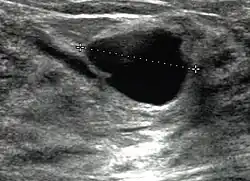

Mammazysten entstehen häufig schnell und können von Patientinnen aufgrund des knotigen Tastbefunds fälschlicherweise für Brustkrebs gehalten werden. Die diagnostische Abklärung erfolgt durch Mammasonographie, bei der sich die Zysten als echoleere, klar umgrenzte Gebilde zeigen, deren Rand keine papillären Strukturen aufweist. In der Mammographie zeigen sich Zysten als scharf begrenzte Strukturen mit angedeutetem Halo-Phänomen. Unter Umständen kann eine Punktion (Feinnadelbiopsie) unter Ultraschallkontrolle mit zytologischer Untersuchung des Sekrets angezeigt sein.